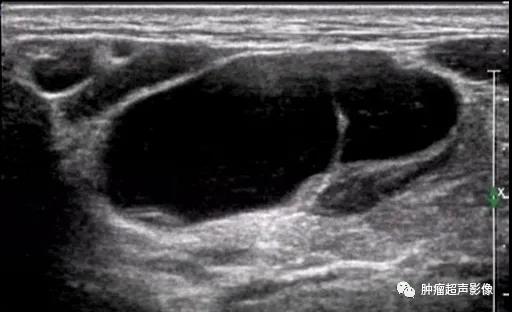

手术证实的口外型舌下腺囊肿:颌下腺周围不规则无回声向口底部延伸,边缘毛糙,无明确的包膜,透声佳,无血流。

手术证实的口外型舌下腺囊肿:颌下区不规则无回声向口底部延伸,下颌舌骨肌有缺损,边缘毛糙,无明确的包膜,透声佳,无血流(来自微信好友会诊病例)。

手术证实的口外型舌下腺囊肿:颌下形态欠规则无回声,大部分边缘光整,口底侧局部边缘毛糙、无明确的包膜,透声欠佳,无血流,比较容易误诊。